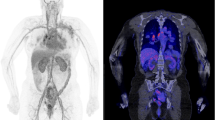

Recent works have reported the feasibility of CT-less approaches for PET attenuation correction using the LSO intrinsic radiation of LAFOV PET-CT scanners to create an initial estimate of the attenuation maps. In particular, Teimoorisichani et al. created improved attenuation maps based on joint activity and attenuation reconstruction algorithms and compared to CT-based PET images [26]. The comparison of both approaches demonstrated a 6.5–8.3% average quantitative error. The same group applied this approach in 18 oncological patients and demonstrated that the mean absolute errors in SUV between the CT-based reconstructed images and the CT-less images were less than 5% in healthy organs, less than 7% in brain gray matter, and 4.3% for all evaluated tumors [27]. Another promising AI-based approach for CT-less attenuation correction for LAFOV PET-CT scanners has been published by Xue et al. [28, 29]. Such approaches may be interesting for longitudinal PET studies within very short time intervals for serial therapy response assessment (Fig. 1a, b and Fig. 2).

a Comparison of a [68Ga]-DOTATOC study in a patient with liver metastases of a neuroendocrine carcinoma with a conventional PET-CT scanner 1 h p.i. (Biograph mCT, upper row) and a LAFOV PET-CT system 2 h p.i. (Biograph Vision Quadra, lower row). Apart from the larger metastatic lesion in the cranial part of the organ, a second smaller liver metastasis is delineated with the LAFOV scanner in the transversal slices despite the delayed scanning due to the higher sensitivity of the new system. b Comparison of the maximum intensity projection (MIP) images of the same patient with both scanners